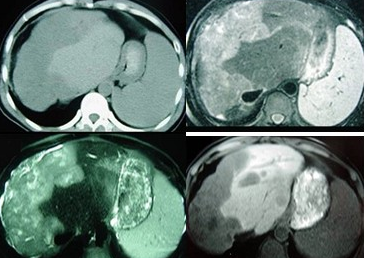

女性,72岁,腹胀不适1年,加重伴恶心呕吐乏力1个月,影像检查如图,最可能的诊断是

A:肝硬化腹水

B:原发性肝癌

C:肝血管瘤

D:巴-希综合征

E:局灶脂肪肝